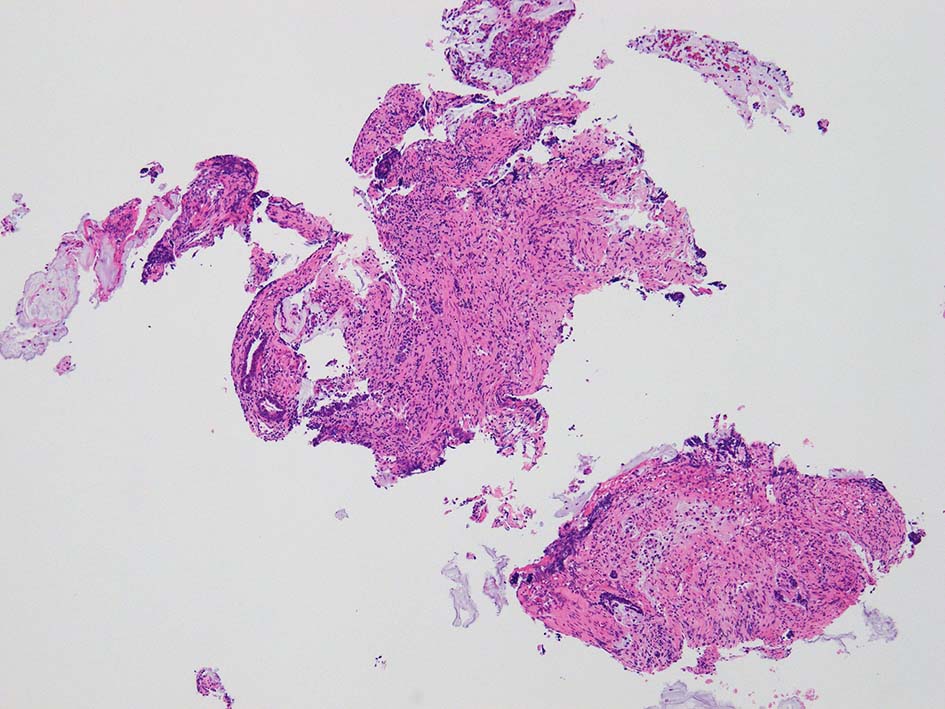

膀胱鏡検査で頸部6時方向に乳頭状腫瘤があり, 膀胱がん疑いで生検をおこなう.

desmoplastic fibrosis, 粘液浸潤のみられる組織片にはsig, porのadenocarcinoma浸潤が確認される.